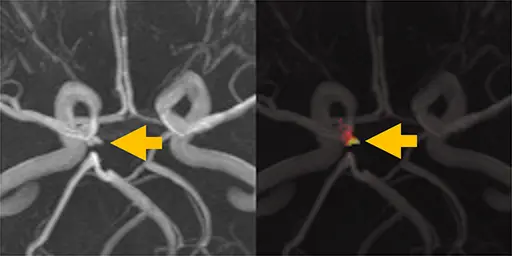

破裂前の動脈瘤 (unruptured aneurysm) を確実に検出することが重要ですが、複雑に分岐する血管の小さな膨隆を発見することは、画像診断専門医にとっても難しいことがあります。

本研究では、convolutional neural network (CNN) を用いた脳動脈瘤の自動検出を試みています。

各ボクセルに対して「そこを中心とする小領域に maximum intensity projection (MIP) を複数方向から適用した画像」を生成し、CNNによって動脈瘤か正常領域かを分類しています。